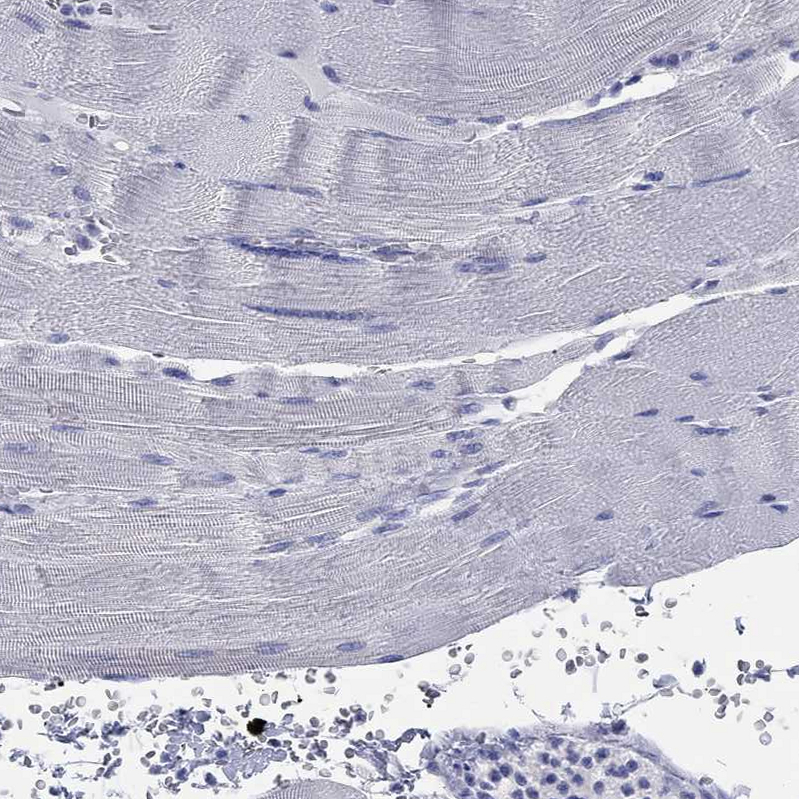

Immunohistochemical staining of human hypothalamus shows strong cytoplasmic positivity in neurons.